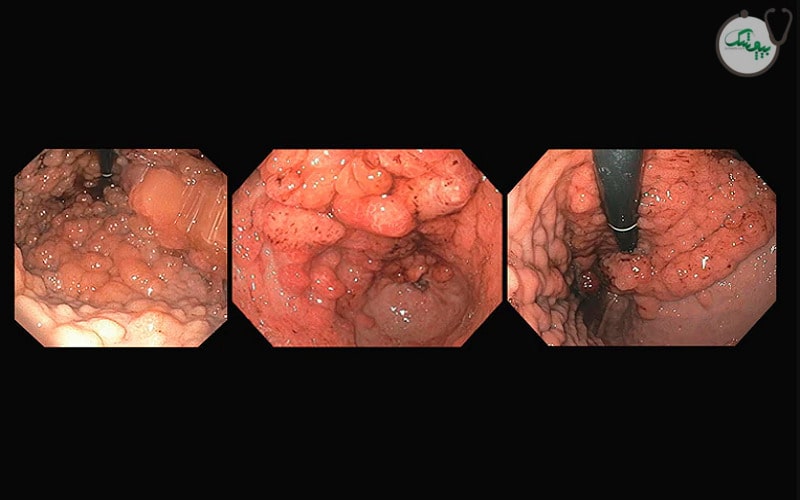

عکس پولیپ معده

تشخیص پولیپ معده

تشخیص پولیپ معده معمولاً در طول آندوسکوپی فوقانی انجام می‌ شود، که در آن یک دوربین انعطاف‌ پذیر وارد معده می شود و امکان مشاهده پوشش معده و هرگونه پولیپ در آن را فراهم می‌ کند. متخصصان، پولیپ‌ ها را بر اساس اندازه، تعداد، شکل و محل قرارگیری ارزیابی می‌ کنند. همچنین در صورت مشاهده پولیپ در طی آندوسکوپی، از بافت آنها نمونه برداری می شود تا نوع پولیپ و خوش خیم، پیش سرطانی یا بد خیم بودن آنها مشخص شود. در اغلب موارد برای تشخیص و ارزیابی پولیپ های معده تصویربرداری استفاده نمی شود، مگر اینکه پولیپ بسیار بزرگ باشد.